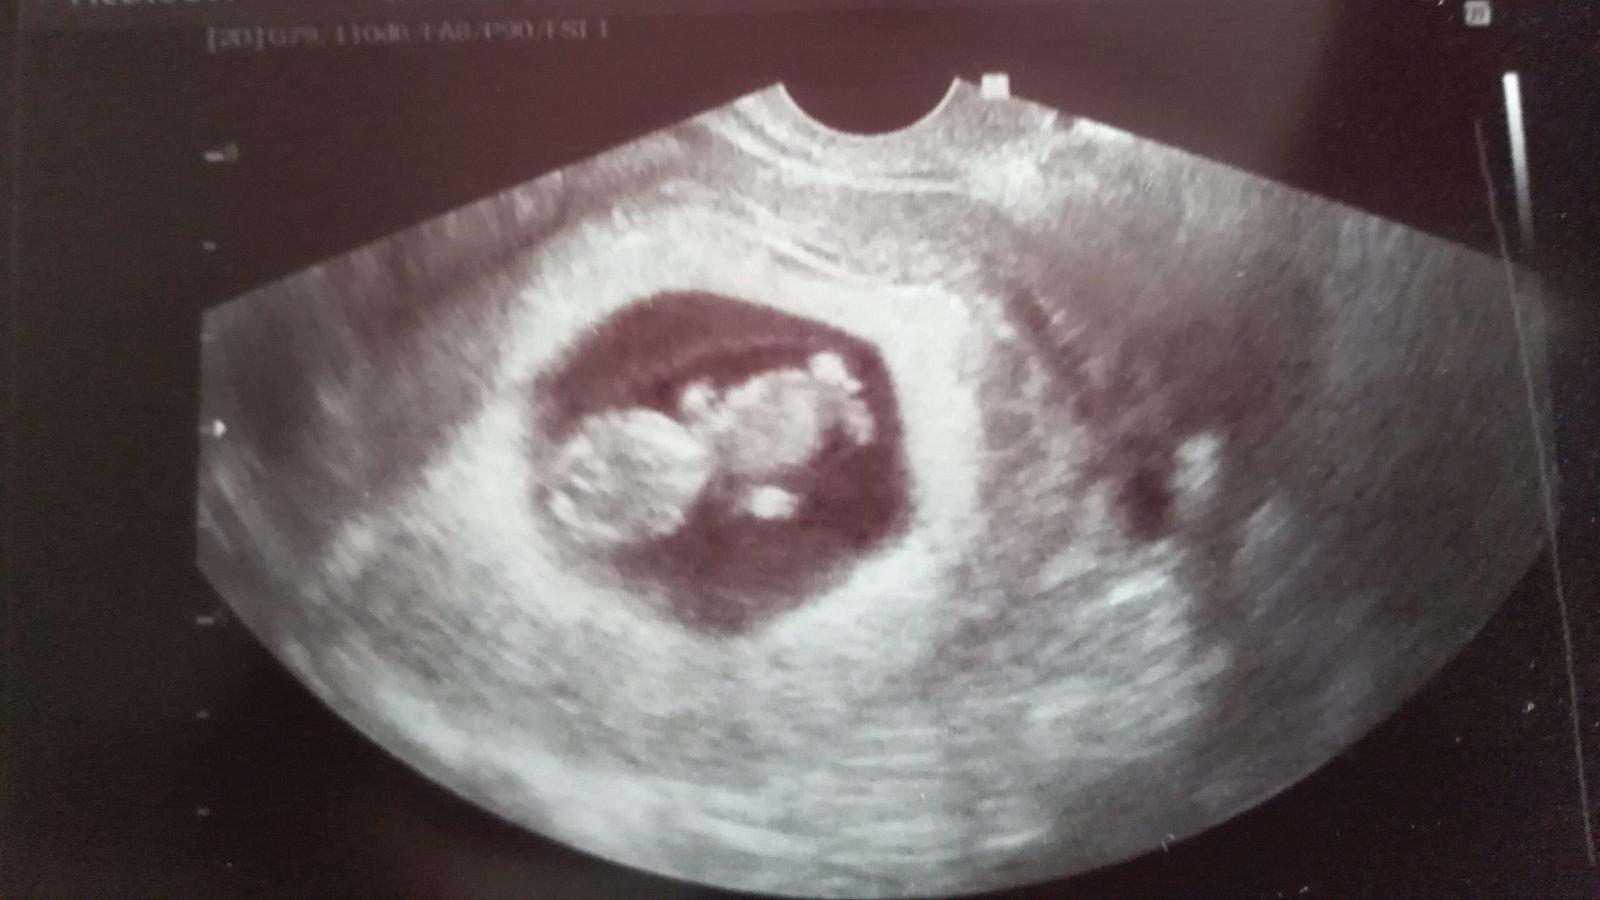

Ahoj dievcata, dnesny uzv dopadol na vybornu, krpec ma 11mm a sme v 7tt 🙂. Srdiecko veselo bije. Dostala som kopec instrukcii, kam vsade musim ist....hematologia, imunologia, ako prevencia. Vzali mi aj stery na bakterie, lebo pred tehu mi nasli ecoli a tie sme nedoriesili. Ja som si spravila vyplach Rosalginom ale iba 1x. Ak sa bacily najdu, supnu mi lieky, Macmiror....citala som vsak, zeby sa v prvom trimestry nemal brat. Dr som sa na to pytala a vraj je to v poriadku, ze kludne mozem. Mala niektora skusenost s tym, ze musela brat nieco taketo?